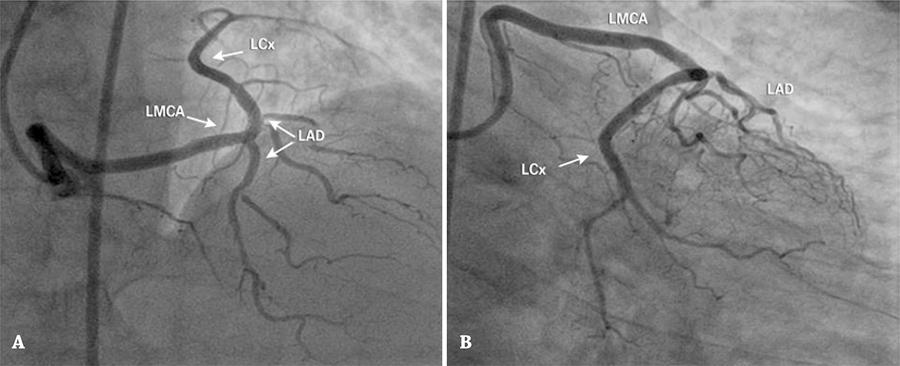

Anomalous coronary arteries are rare. The origin of the left main coronary artery from the right sinus of Valsalva is related to some events, such as syncope, arrhythmias, angina, among others. By and large, its diagnosis is incidentally made by coronary angiography. The presence of this type of anomaly may hinder percutaneous approach of the coronary lesions. The authors describe a case of left main coronary artery originating from the right sinus of Valsalva, associated to disease of multiple vessels. After discussing the case with the patient and family, the cath lab team performed a successful percutaneous coronary intervention.